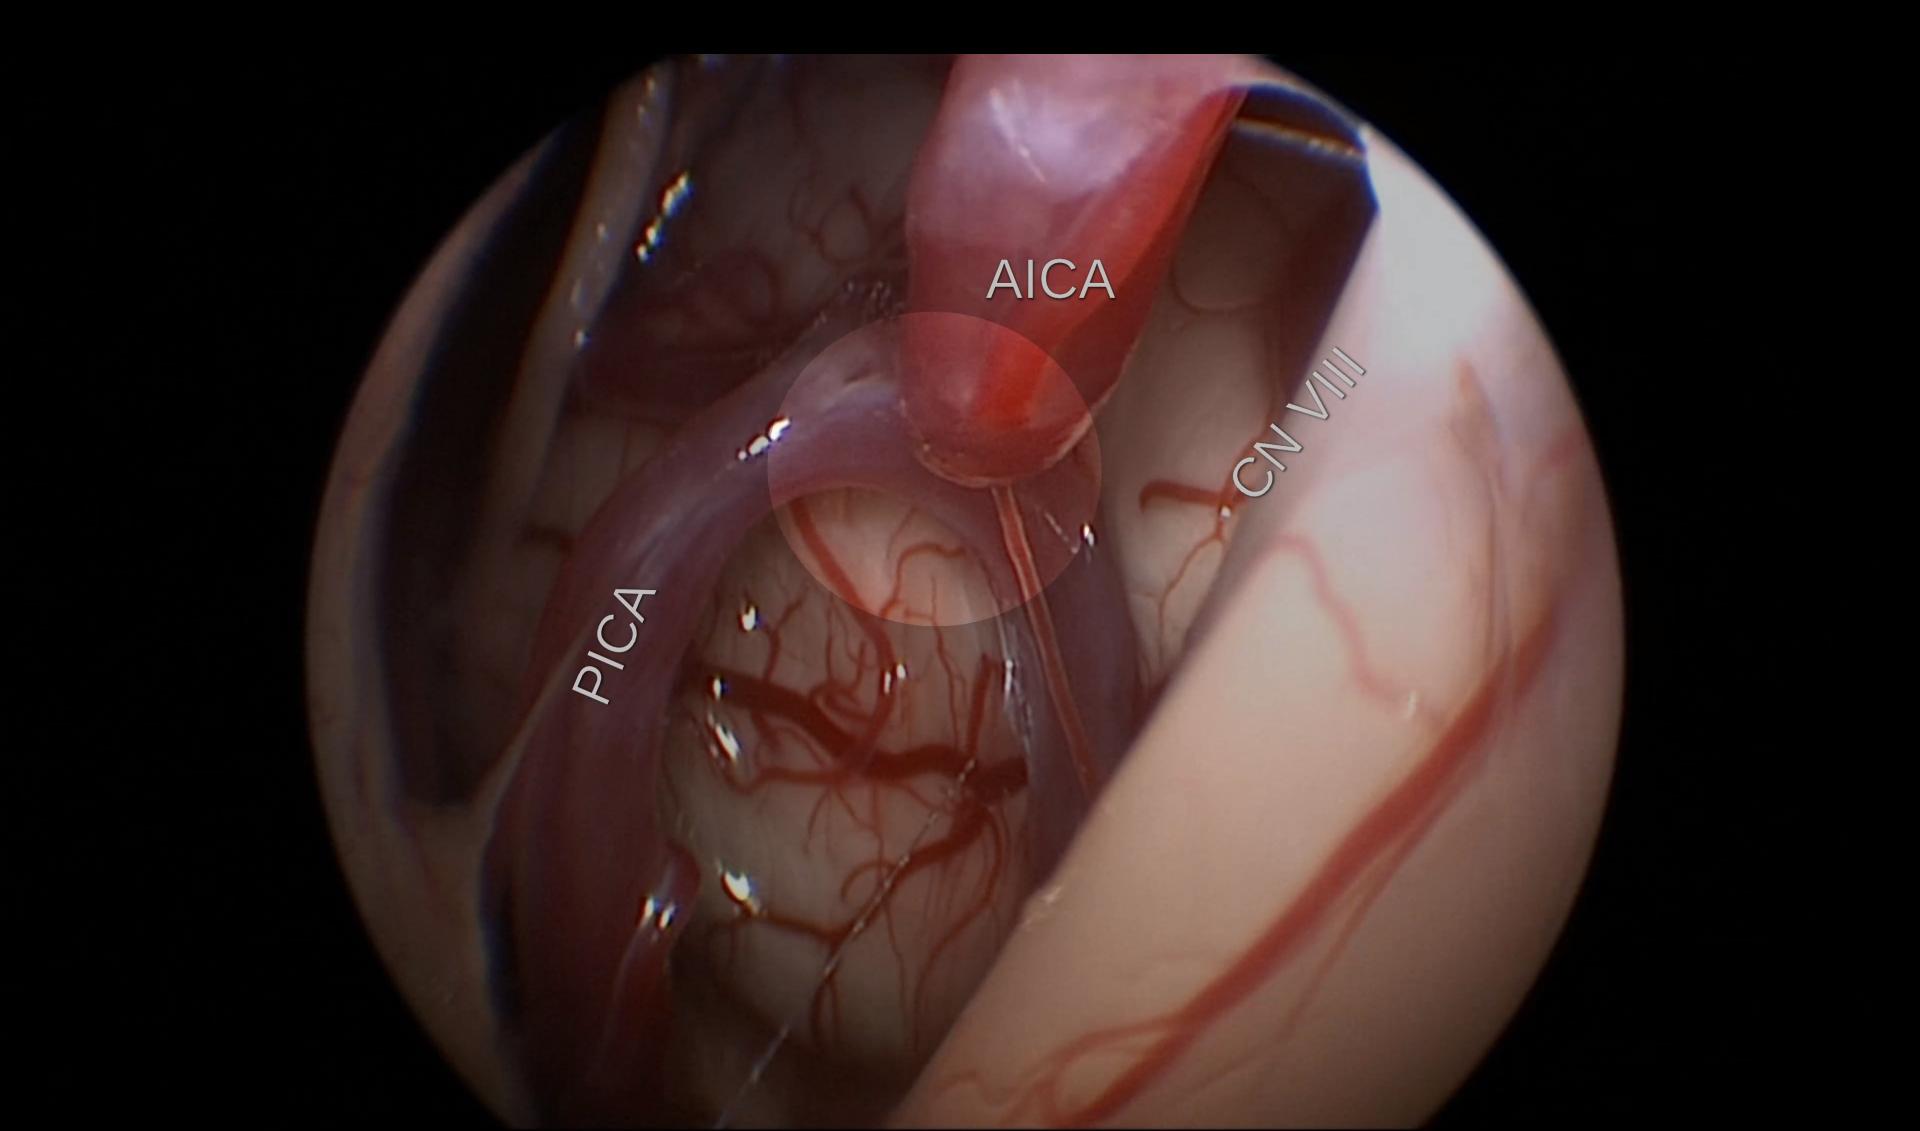

Chirurgisch

Bei einem vorliegenden neurovaskulären Konflikt kann dieser auch durch einen chirurgischen Eingriff behandelt werden. Hierbei wird der neurovaskuläre Konflikt aufgehoben. Dies kann beispielsweise mit einem Stück autologer Muskulatur[^10], Teflon[^9] [^13], Ivalon[^11] oder Goretex[^12] erreicht werden.

Der neurovaskuläre Konflikt ist in den meisten Fällen in der Root Exit Zone (REZ) des Nervus facialis lokalisiert[^3]. Neurovaskuläre Konflikte des Nervus facialis distal der Root Exit Zone sind selten!

microvascular_decompression_hemifacial_spasm.mp4 180.93 MB

- Video Beschreibung

- Operatives Video einer Endoskop-assistierte mikrovaskuläre Dekompression des Nervus facialis.

- Lizenz

- CC BY 4.0